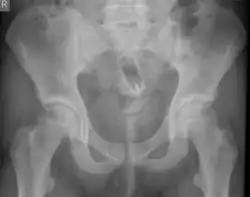

Обычно делают несколько рентгеновских снимков, чтобы точно определить место нахождения инородного тела. Инородные тела из малоконтрастного материала (например, пластика) могут потребовать ультразвукового исследования или компьютерной томографии.[28] Магнитно-резонансная томография противопоказана, особенно если неизвестен материал инородного тела. Инородные тела прямой кишки могут проникать глубоко в толстую кишку, при определённых обстоятельствах вплоть до правого изгиба ободочной кишки.[9]